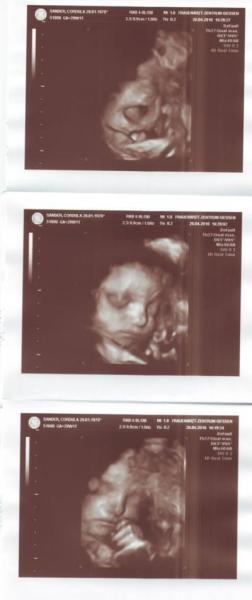

4D Ultraschall haben wir auch wieder gemacht - man was ist das immer faszinierend! Und in 2 Wochen macht er dann nochmal 4D mit. Dann bekomm ich auch die DVD von den 3x... hach wie spannend :-)

Hab ein Foto angehängt... auf dem ersten gähnt sie ganz herzhaft